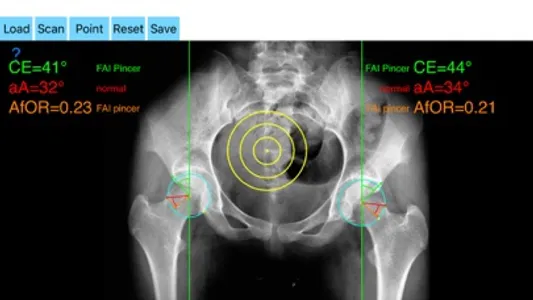

The drawn lines between points, allows app to estimate in radiographs, Center-Edge Angle (CE), α - angle (aA) and the anterior femoral offset ratio (AfOR). The measured values are compared with values from normal reference database. In case the measured angles are beyond the normal range, the hip is categorized as normal, dysplastic, borderline dysplastic hip and the type of femoroacetabular impingement (FAI) deformity namely cam type, pincer type or mixed is printed over the screen accordingly. Measures by the app are not affected by the X-ray projection.